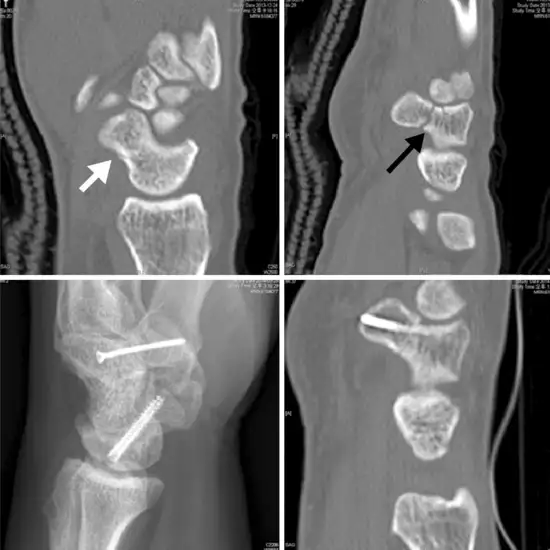

The scaphoid is one of the small carpal bones of the wrist on the thumb side. For the motion and stability of the wrist, this bone plays an important role. Because of a fall onto an outstretched hand, a scaphoid fracture occurs. To detect/diagnose a scaphoid fracture, the location of the scaphoid in the left wrist, CT Left Scaphoid is recommended.

• To detect the location of scaphoid bone and to see whether the bone is displaced or not.

• To plan for treatment of the scaphoid fracture.